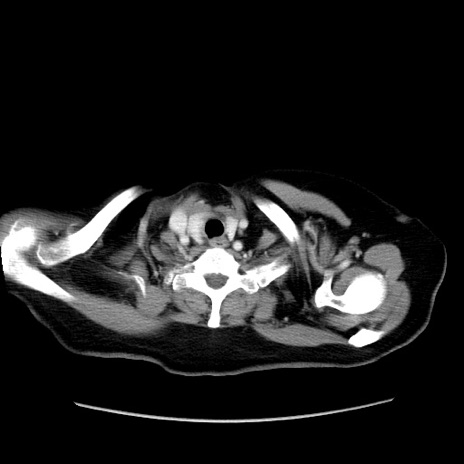

冠状断像

症例19(横断像)

【症例】80歳代女性

【主訴】下腹部痛

【現病歴】約8時間前より下腹部痛の出現あり、救急外来受診。

【既往歴】両側付属器切除

【身体所見】意識清明、下腹部正中に手術痕あり、その部位に一致して圧痛と反跳痛あり。腸蠕動音は亢進。

【データ】WBC 9300、CRP 0.15